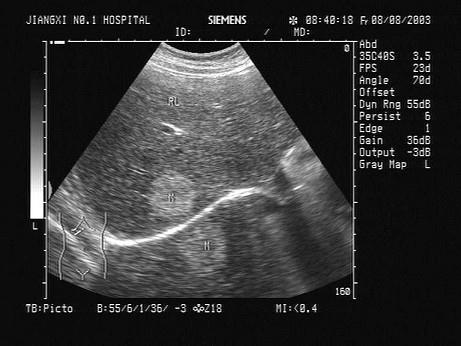

问题 如图所示,是超声波的何种伪像?(?)

选项 A.镜面效应 B.振铃效应 C.旁瓣效应 D.部分容积效应 E.声影

答案 A